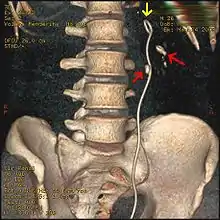

Three-dimensional reconstructed CT scan image of a ureteral stent in the left kidney (indicated by yellow arrow), with a kidney stone in the inferior renal pelvis (highest red arrow) and one in the ureter beside the stent (lower red arrow)

Most stones under 5 mm (0.2 in) pass spontaneously.[29][7] Prompt surgery may, nonetheless, be required in persons with only one working kidney, bilateral obstructing stones, a urinary tract infection and thus, it is presumed, an infected kidney, or intractable pain.[100] Beginning in the mid-1980s, less invasive treatments such as extracorporeal shock wave lithotripsy, ureteroscopy, and percutaneous nephrolithotomy began to replace open surgery as the modalities of choice for the surgical management of urolithiasis.[7] More recently, flexible ureteroscopy has been adapted to facilitate retrograde nephrostomy creation for percutaneous nephrolithotomy. This approach is still under investigation, though early results are favorable.[101] Percutaneous nephrolithotomy or, rarely, anatrophic nephrolithotomy, is the treatment of choice for large or complicated stones (such as calyceal staghorn calculi) or stones that cannot be extracted using less invasive procedures.[47][7]

Ureteroscopic surgery

Ureteroscopy has become increasingly popular as flexible and rigid fiberoptic ureteroscopes have become smaller. One ureteroscopic technique involves the placement of a ureteral stent (a small tube extending from the bladder, up the ureter and into the kidney) to provide immediate relief of an obstructed kidney. Stent placement can be useful for saving a kidney at risk for postrenal acute kidney failure due to the increased hydrostatic pressure, swelling and infection (pyelonephritis and pyonephrosis) caused by an obstructing stone. Ureteral stents vary in length from 24 to 30 cm (9.4 to 11.8 in) and most have a shape commonly referred to as a "double-J" or "double pigtail", because of the curl at both ends. They are designed to allow urine to flow past an obstruction in the ureter. They may be retained in the ureter for days to weeks as infections resolve and as stones are dissolved or fragmented by ESWL or by some other treatment. The stents dilate the ureters, which can facilitate instrumentation, and they also provide a clear landmark to aid in the visualization of the ureters and any associated stones on radiographic examinations. The presence of indwelling ureteral stents may cause minimal to moderate discomfort, frequency or urgency incontinence, and infection, which in general resolves on removal. Most ureteral stents can be removed cystoscopically during an office visit under topical anesthesia after resolution of urolithiasis.[102]